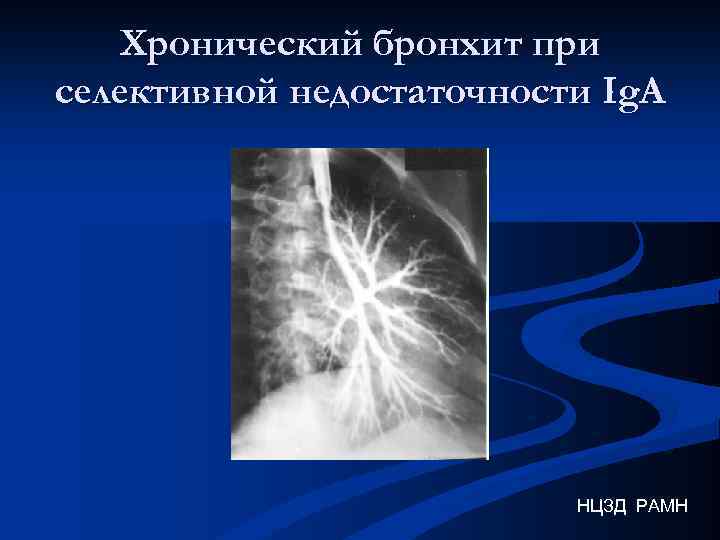

Хронический бронхит при селективной недостаточности Ig. A НЦЗД РАМН